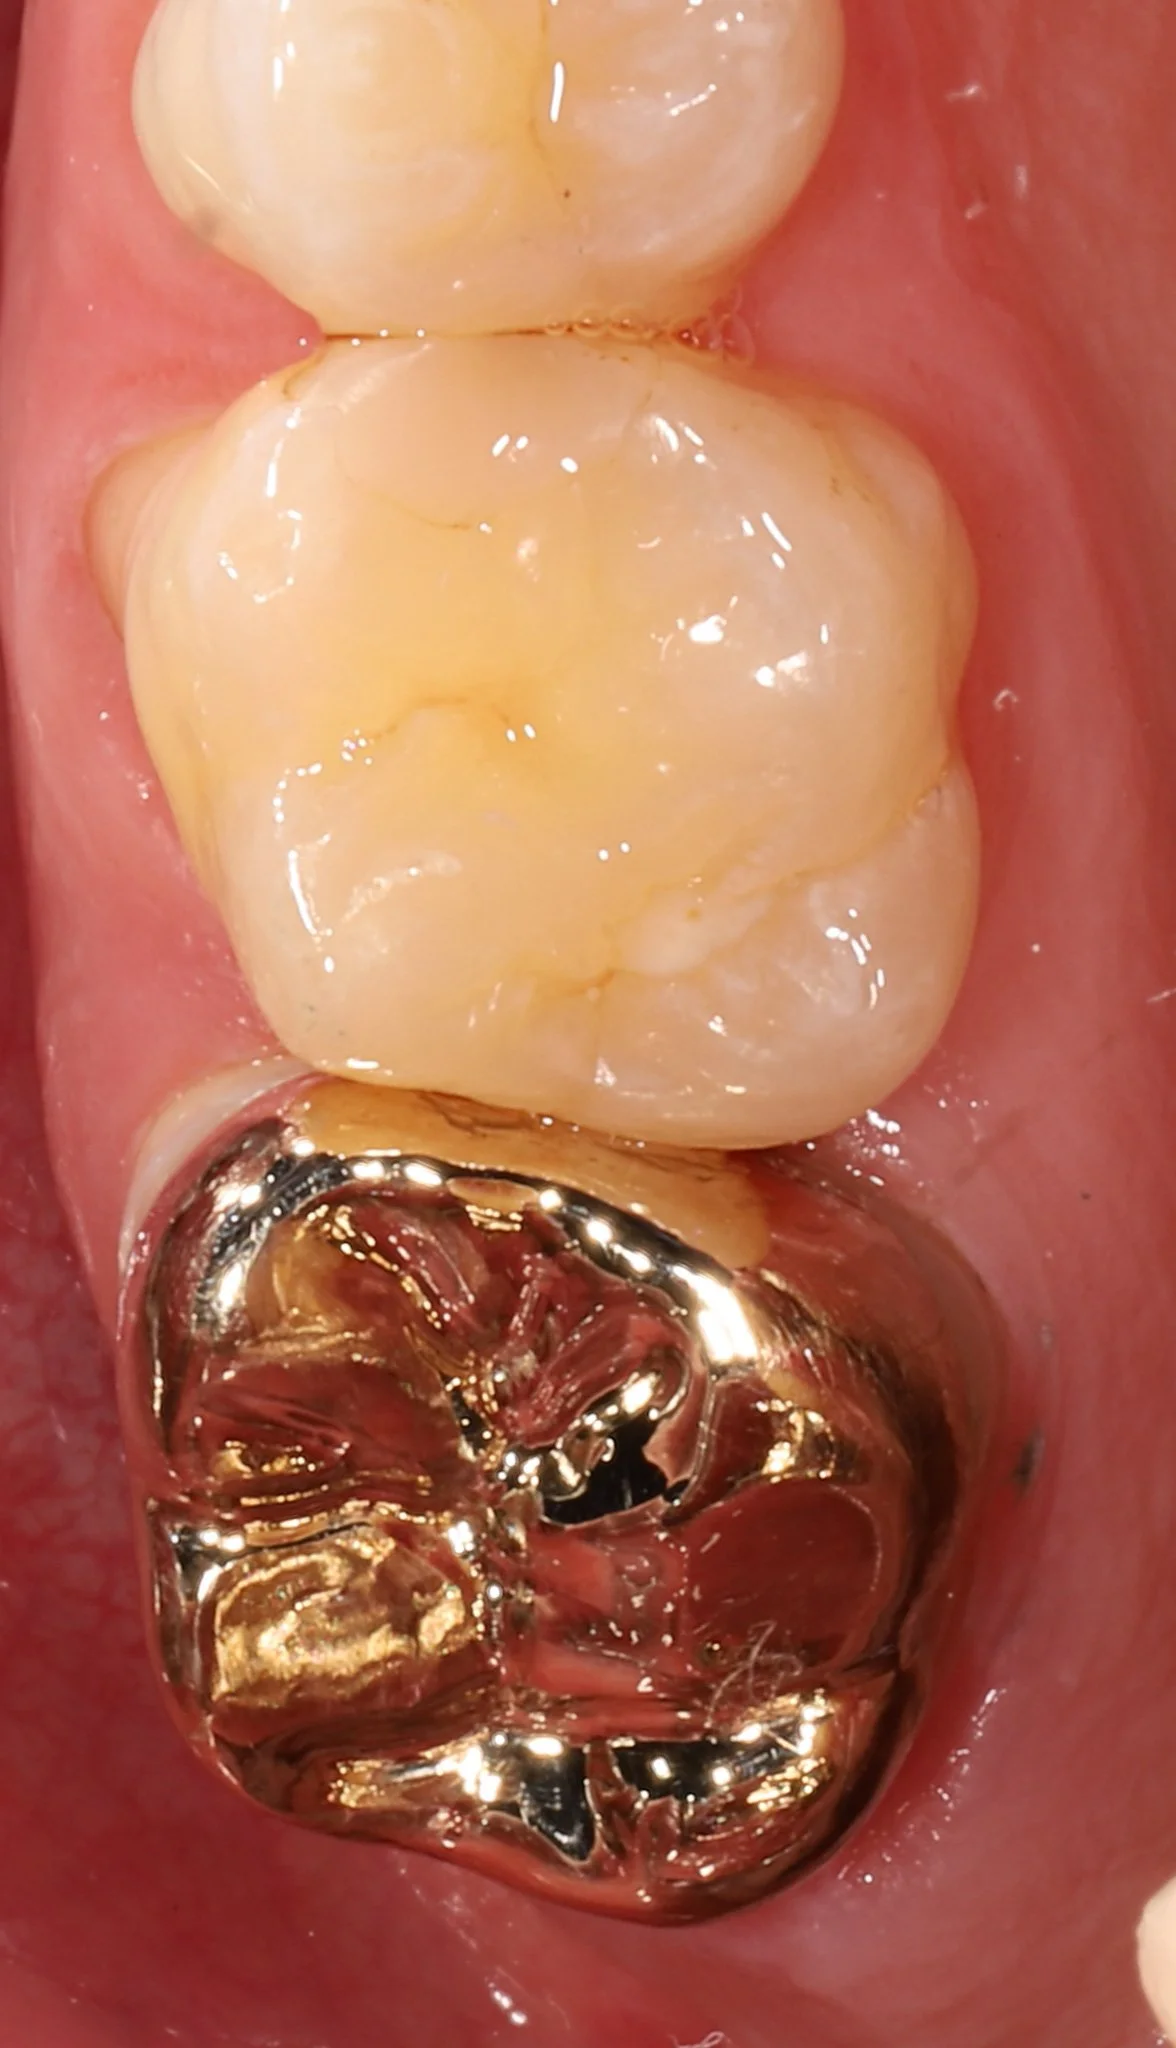

Close-up of the lower molars in a person's mouth, showing a gold dental filling on the bottom molar and the other teeth are natural and clean.

Gold Restoration

Close-up of lower molars with gold dental crowns and fillings.

Combination of gold inlay, onlay and a bonded porcelain restoration